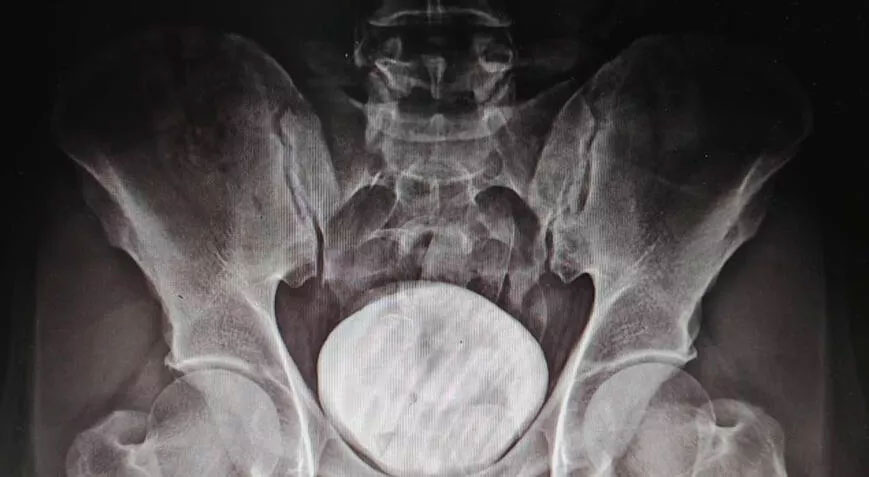

Kars Harakani Devlet Hastanesi’ne götürülen Tazehkand’ın çekilen röntgeninde, makatında uyuşturucu tespit edildi. Uyuşturucuyu doğal yollardan çıkaran Tazehkand, gözaltına alındı. Emniyetteki işlemlerinin ardından adliyeye sevk edilen şüpheli, çıkarıldığı hakimlikçe tutuklandı.